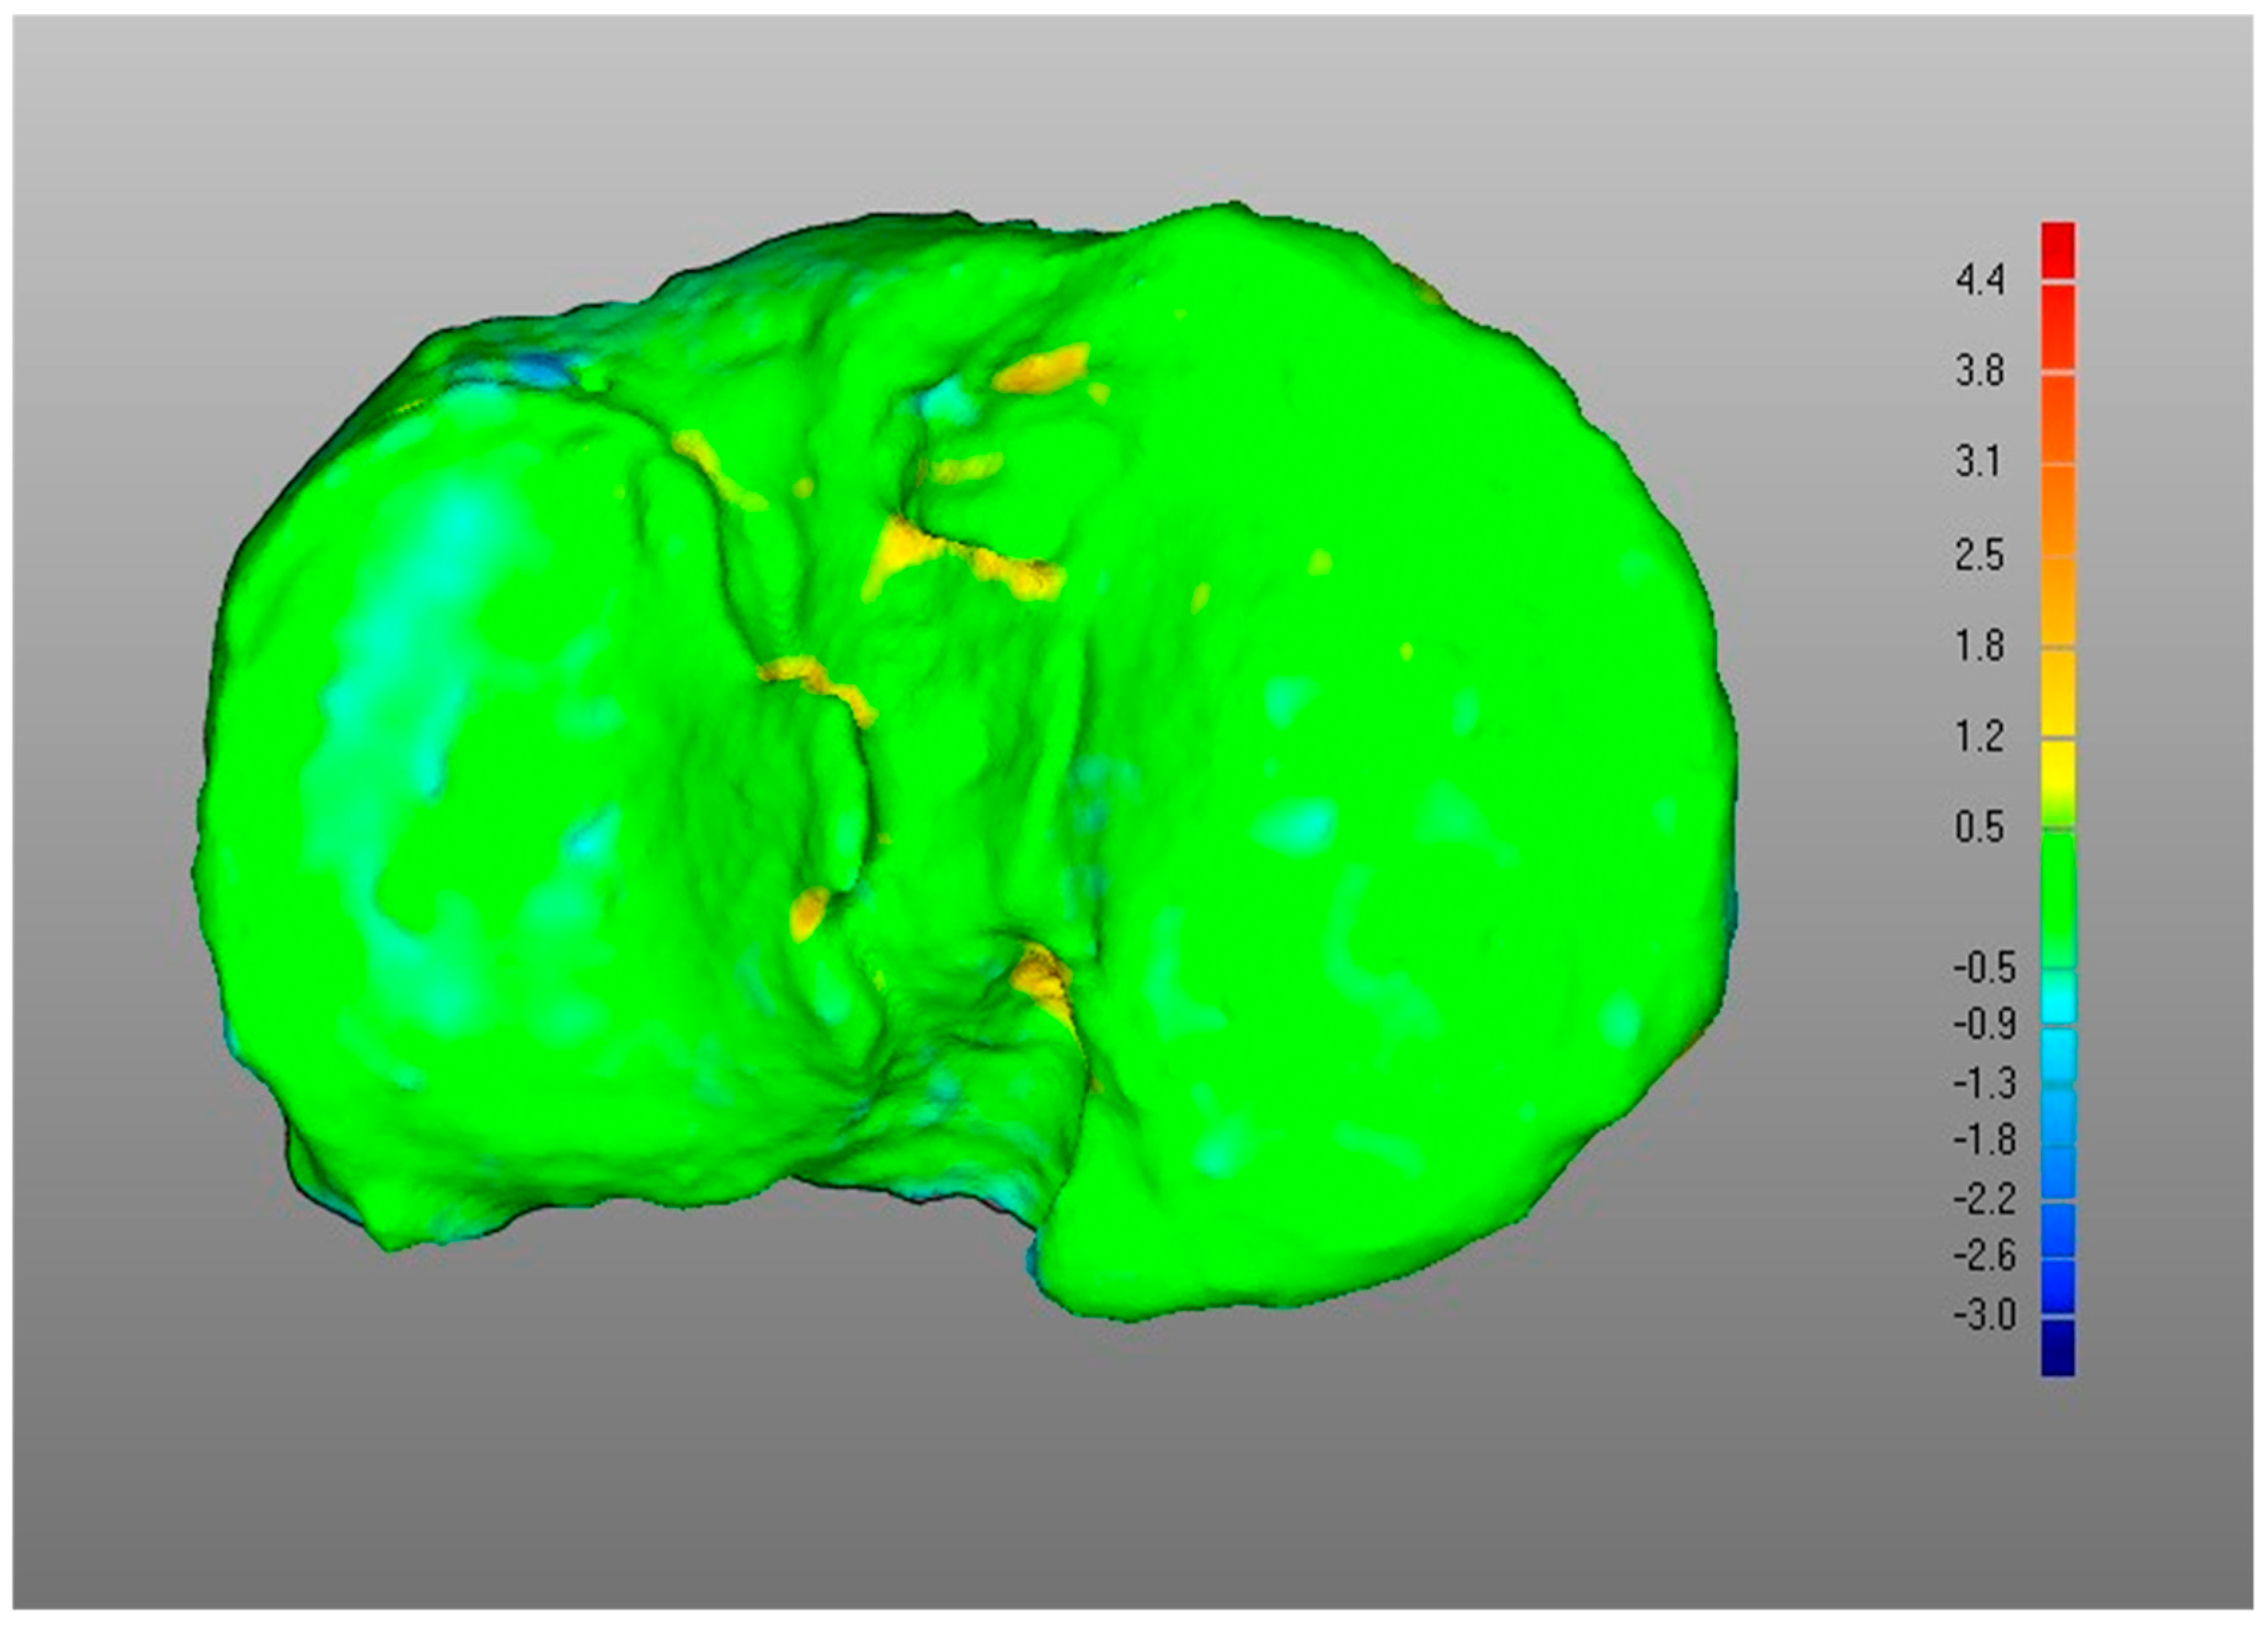

- Overall, a good replication of PLA tibia morphology was achieved in POST (Figure 3 and Figure 4), with average values for of 1.4 mm and of −0.9 mm, associated with very small DMA standard deviation (DSD average value 1.6 mm) over the entire patient cohort (Table 1). Most points were in the safe zone (Table 2), although discrepancies were observed, mainly due to the difficulty of excluding the bone allograft (used to fill the osteotomy cut which is the standard practice of the operating surgeon) during image segmentation, thus altering the morphology of the area around the osteotomy in POST with reference to the corresponding one in PLA.Table 1. DMA outputs (units for all variables mm). = Positive mean Distance, = Negative mean Distance, DSD = DMA standard deviation.Table 1. DMA outputs (units for all variables mm). = Positive mean Distance, = Negative mean Distance, DSD = DMA standard deviation.